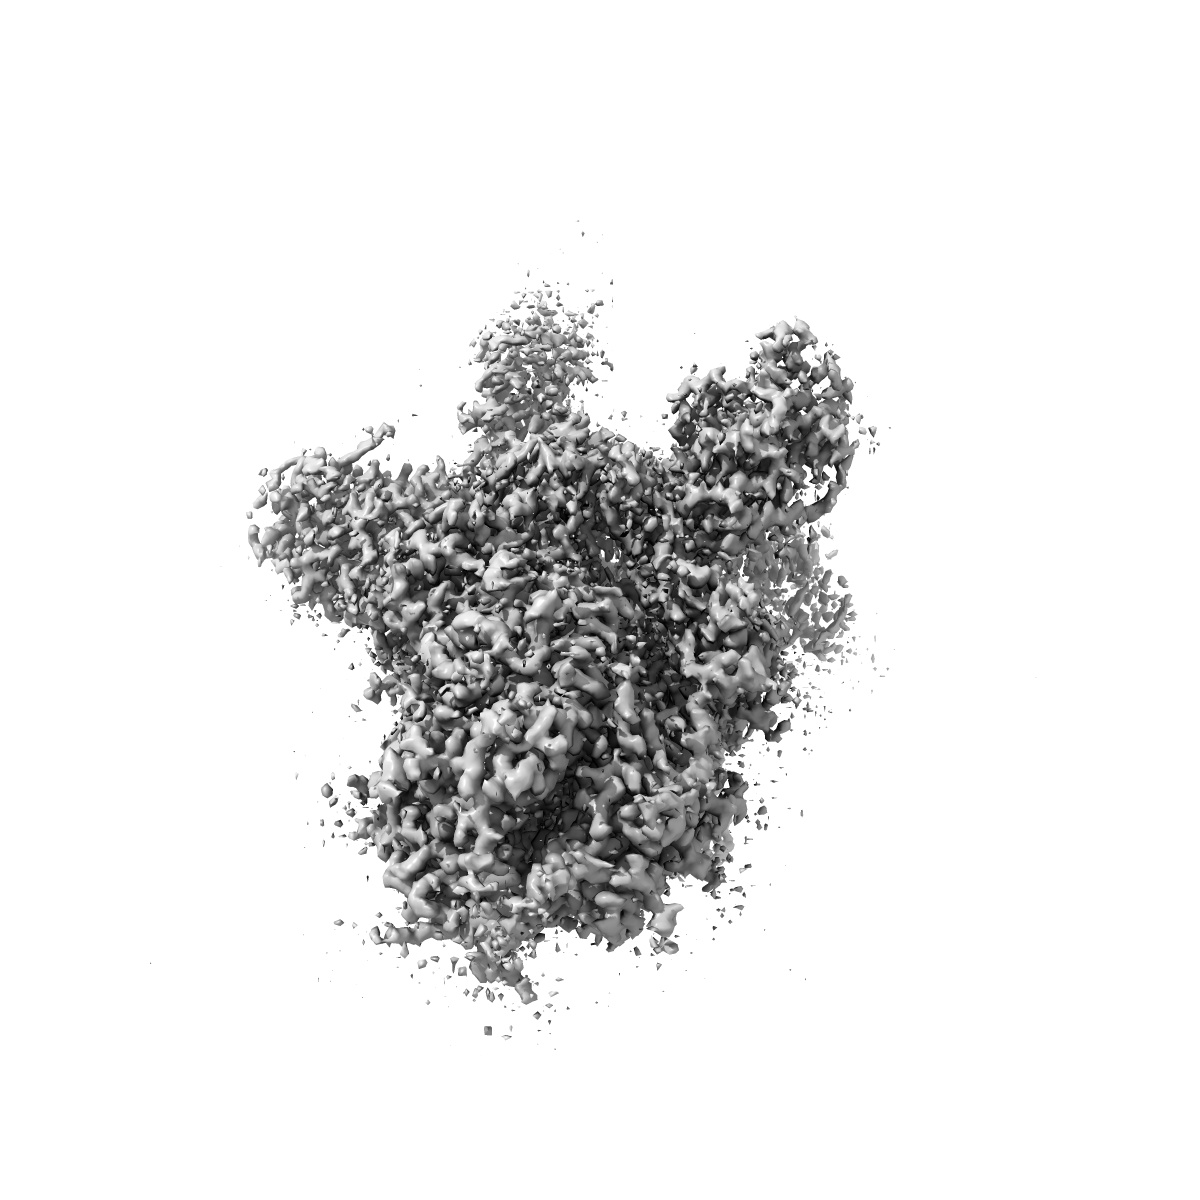

EMD-32920

S protein of SARS-CoV-2 in complex with 2G1

Single-particle2.7 Å

Sample: S protein of SARS-CoV-2 in complex with 2G1

Fitted models: 7x08

Broad ultra-potent neutralization of SARS-CoV-2 variants by monoclonal antibodies specific to the tip of RBD.